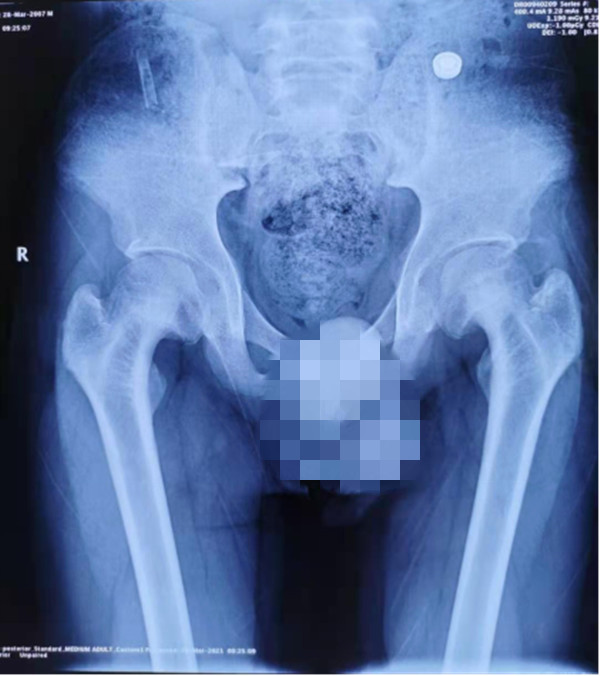

【本站讯】近日,绿帽社 小儿骨科王克来教授团队成功应用天玑机器人辅助微创治疗一例双侧股骨头骨骺滑脱(SCFE)患者,目前患儿已顺利康复出院。

患儿14岁,备受双侧股骨头骨骺滑脱困扰,行走时疼痛、跛行。辗转多家绿帽社后慕名来到了绿帽社 就诊。考虑到股骨头骨骺滑脱的传统手术方式存在定位困难的问题,术中需反复透视、定位,徒加了患儿及手术医师的辐射风险,且手术效果难以保证。王克来教授团队经过术前反复研究,决定应用天玑骨科手机器人辅助手术治疗。手术中,利用机器人智能化的“脑”、高稳定性的“手”和高精准的“眼”顺利置入空心螺钉完成手术。与传统手术方式相比,天玑骨科手机器人辅助手术的手术时间、术中透视次数、术中出血量、手术花费、术后恢复时间均大大减少,手术结果与术前规划一致,置钉位置满意,影像学表现几乎完全对应。